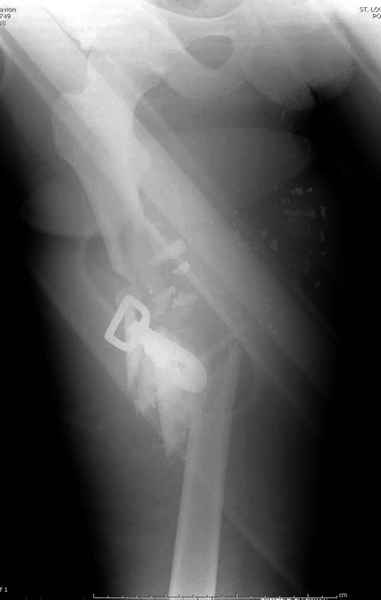

2 перелом бедра

Имя     : 2 GSW exfix.jpg

Тип     : image/jpeg

Размер  : 16470 байтов

Описание: отсутствует

Url     : http://weborto.net:8080/pipermail/ortho/attachments/20090726/b21ae3ea/attachment-0016.jpg

----------- УМЕДХЭБС ЮБУФШ -----------

Вложение не в текстовом формате было извлечено…

Имя     : 3 GSW final ap.jpg

Размер  : 25174 байтов

Url     : http://weborto.net:8080/pipermail/ortho/attachments/20090726/b21ae3ea/attachment-0017.jpg

Имя     : 4 GSW final lat.jpg

Размер  : 18190 байтов

Url     : http://weborto.net:8080/pipermail/ortho/attachments/20090726/b21ae3ea/attachment-0018.jpg